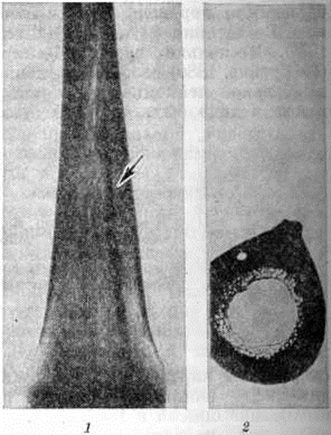

Острый миелобластный лейкоз в развёрнутой стадии болезни характеризуется выраженной лейкозной инфильтрацией костного мозга и других органов. В печени лейкозные разрастания локализуются в синусоидных капиллярах и в области портальных трактов. Аналогичное расположение инфильтратов имеется и при других более редких формах острого Лейкозы (монобластном, миеломонобластном, недифференцируемом, промиелоцитарном и другие), поэтому данный признак не может служить основанием для разграничения форм острого Лейкозы В лёгких лейкозная инфильтрация обычно выявляется по ходу межальвеолярных перегородок с выходом бластных клеток в просветы альвеол (рисунок 3), возможна локализация и в окружности бронхов, сосудов, междольковых перегородках. У детей при этой форме Лейкозы лейкозные разрастания в вилочковой железе располагаются в соединительнотканных прослойках, сдавливают дольки, что сопровождается увеличением количества аргирофильных волокон. У взрослых типично развитие множественных узлов в надкостнице плоских и трубчатых костей, почках, печени, половых железах, жировой клетчатке (подкожной, ретробульбарной, клетчатке большого сальника и малого таза), иногда в коже, конъюнктиве, твёрдой мозговой оболочке и костном мозге. В ряде случаев в области опухолевых узлов и системных поражений имеется зелёное окрашивание ткани (хлоролейкоз). Аналогичные изменения могут выявляться и при Лейкозы у детей.

При микроскопическом исследовании в костном мозге преобладают незрелые и зрелые клетки гранулоцитарного ряда (рисунок 5), соотношение которых может варьировать. По данным трепанобиопсий, в начальной стадии заболевания ещё в достаточном количестве сохраняются элементы эритропоэтического и мегакариоцитарного ряда. По мере прогрессирования процесса их число снижается, исчезают жировые клетки. Характерны глубокие изменения в строме в виде сочетания процессов деструкции с увеличением количества фибробластов, аргирофильных и иногда коллагеновых волокон. Изучение костного мозга методом трепанобиопсии в динамике свидетельствует о том, что миелофиброз постепенно нарастает и бывает более выражен у больных с повторными ремиссиями и обострениями заболевания. В отдельных случаях в костном мозге имеют место обширные очаги некроза; постоянно наблюдается выраженное рассасывание костной ткани. В селезёнке и лимфатических узлах в развёрнутой стадии болезни обнаруживается диффузная инфильтрация миелоидными элементами, атрофия лимфатической ткани. Лейкозное поражение селезёнки часто сопровождается выраженным в различной степени фиброзом красной пульпы, образованием полей склероза, что наряду с инфильтрацией и полнокровием является причиной увеличения её веса. Для хронический миелолейкоза характерна локализация лейкозных инфильтратов в печени по ходу синусоидных капилляров (рисунок 6), в лёгких — в области межальвеолярных перегородок. Нередко наблюдается инфильтрация стенок мелких бронхов, сосудов, плевры. Реже, чем при острых Лейкозы очаги лейкозной инфильтрации возникают в почках, мышце сердца, в стенках желудочно-кишечные тракта, в оболочках и веществе головного мозга, коже, железах внутренней секреции и других органах.